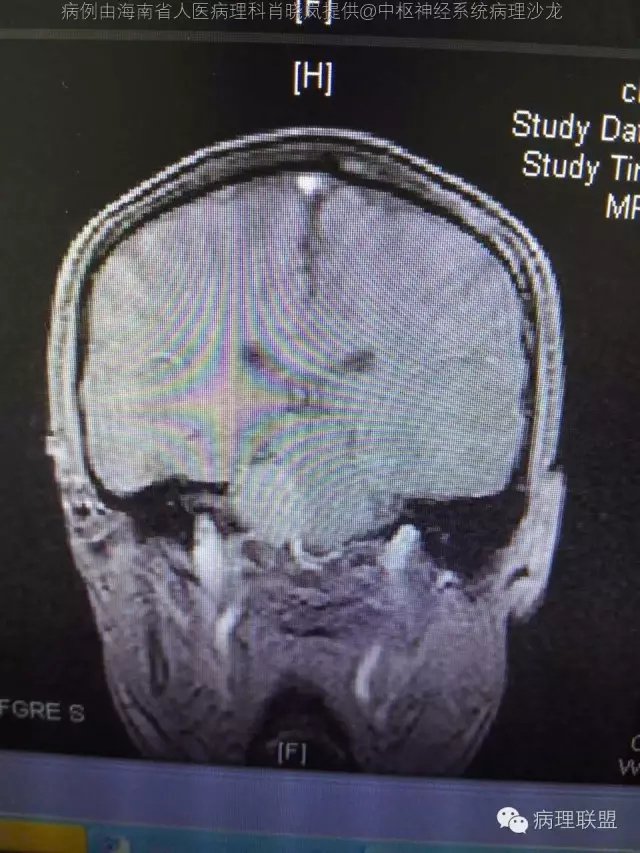

男,36岁。右面部麻木1月余。手术所见:右CPA区见5Ⅹ4cm肿块,灰褐色,血供丰富,质韧,界清。临床诊断:右侧桥小脑角区占位:脑膜瘤。大体检查:灰黑色碎组织一堆,大小2.5Ⅹ2.5x0.5cm,免疫S100,HMB45阳性。Ki67指数低。(病例由海南省人医病理科肖晓岚提供,致谢!)

@海南省人医病理科肖晓岚 影像也是符合黑色素相关肿瘤,可请影像专业的老师分析一下CT结合MR对产生黑色素的病变还是具有一定的特征性的,本例黑色素含量似乎不太多,所以跟脑膜瘤差不太多了,需要请影像老师分析!